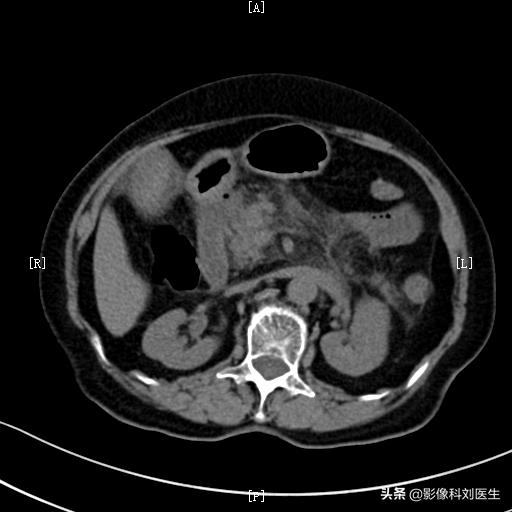

3、腹部CT检查。是诊断胰腺炎最重要的影像学检查。它可以观察胰腺肿大的情况,胰腺周围的渗出情况,通过三期增强扫描,可以判断胰腺组织内是否有坏死,周围是否有假性囊肿形成等。通过CT检查,可以明确急性胰腺炎的分型,了解其并发症情况,对其严重程度进行分级,所以是诊断急性胰腺炎的最佳方法。

急性水肿型胰腺炎:胰腺肿大,边缘毛糙,见多发条索影。

同一病人:胰周脂肪间隙模糊

正常胰腺